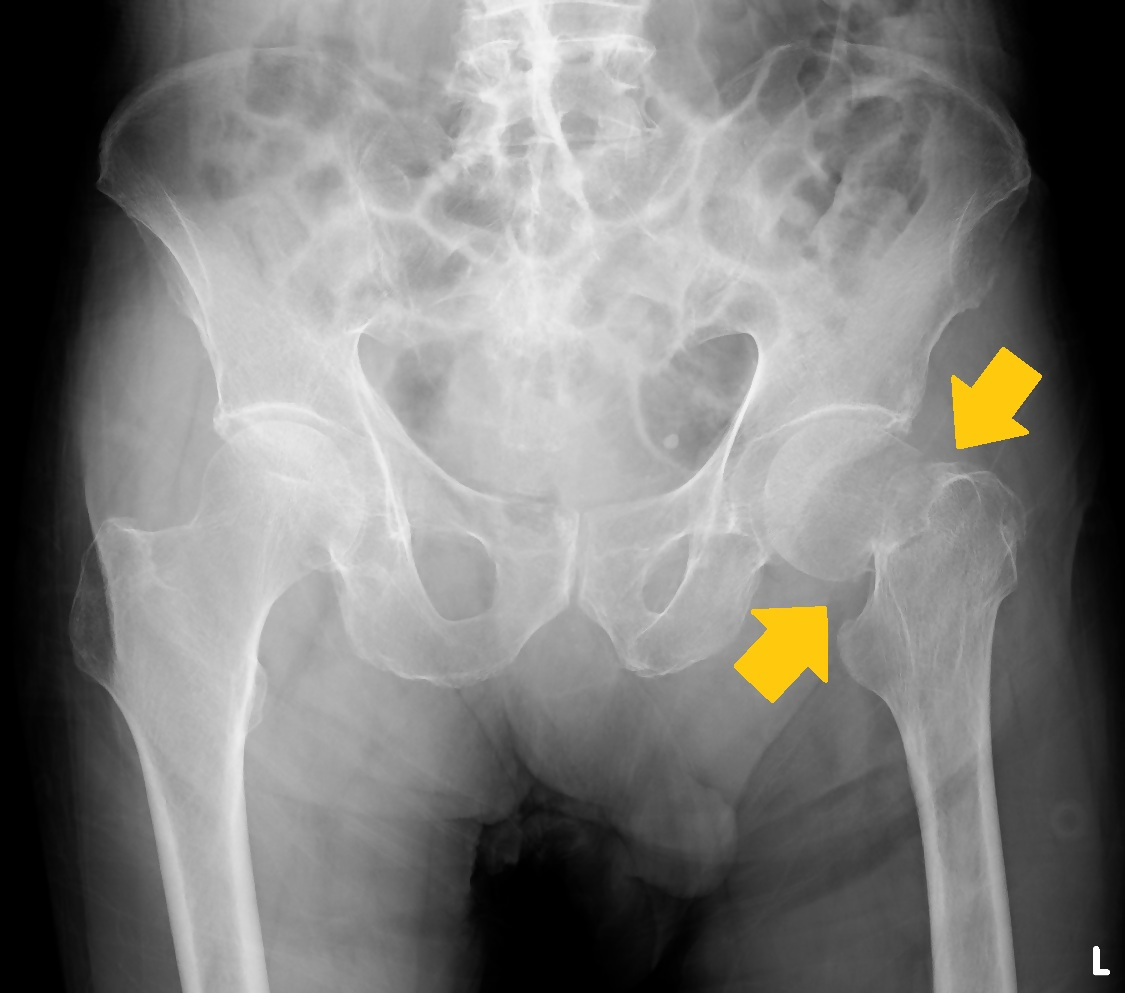

※矢印部分(大腿骨頸部)に骨折線が確認できます

大腿骨頸部骨折とは、股関節の内側にある頸部(けいぶ)と呼ばれる部分が骨折することを言います。

大腿骨の先端の丸い部分を骨頭、そのすぐ下の細い部分が頸部であり、この細い頸部が折れるのが大腿骨頸部骨折です(広義には大腿骨近位端の骨折全体を指すこともありますが、狭義では関節内におこる骨折を指します)。